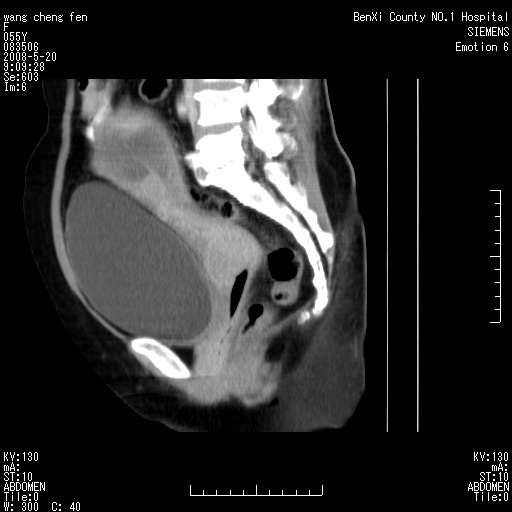

左侧附件区巨大囊实性病灶,边缘光整,病灶囊壁较厚,增强示囊壁及实性部分明显强化,强化呈度与宫体实质大致相同,宫腔积液征像,未见盆腔积液等其他异常,考虑左侧卵巢囊腺癌,不除外囊腺瘤及浆膜下肌瘤坏死

左侧附件区巨大囊实性病灶,边缘光整,病灶囊壁较厚,增强示囊壁及实性部分明显强化,强化呈度与宫体实质大致相同,宫腔积液征像,未见盆腔积液等其他异常。绝经后阴道流血3个月,结合病史左侧卵巢囊腺癌首先考虑,宫腔扩大不除外累及。期待结果。

囊实性肿块分隔厚度较大,厚薄不均,增强实性成分明显强化,有不规则阴道流血,卵巢囊腺癌可能性大。

1,宫颈部占位,宫颈癌?2,左侧附件区囊实性占位,界较清,实质部分强化明显。考虑浆膜下或阔韧带肌瘤囊变可能大。囊腺类肿瘤不除外。